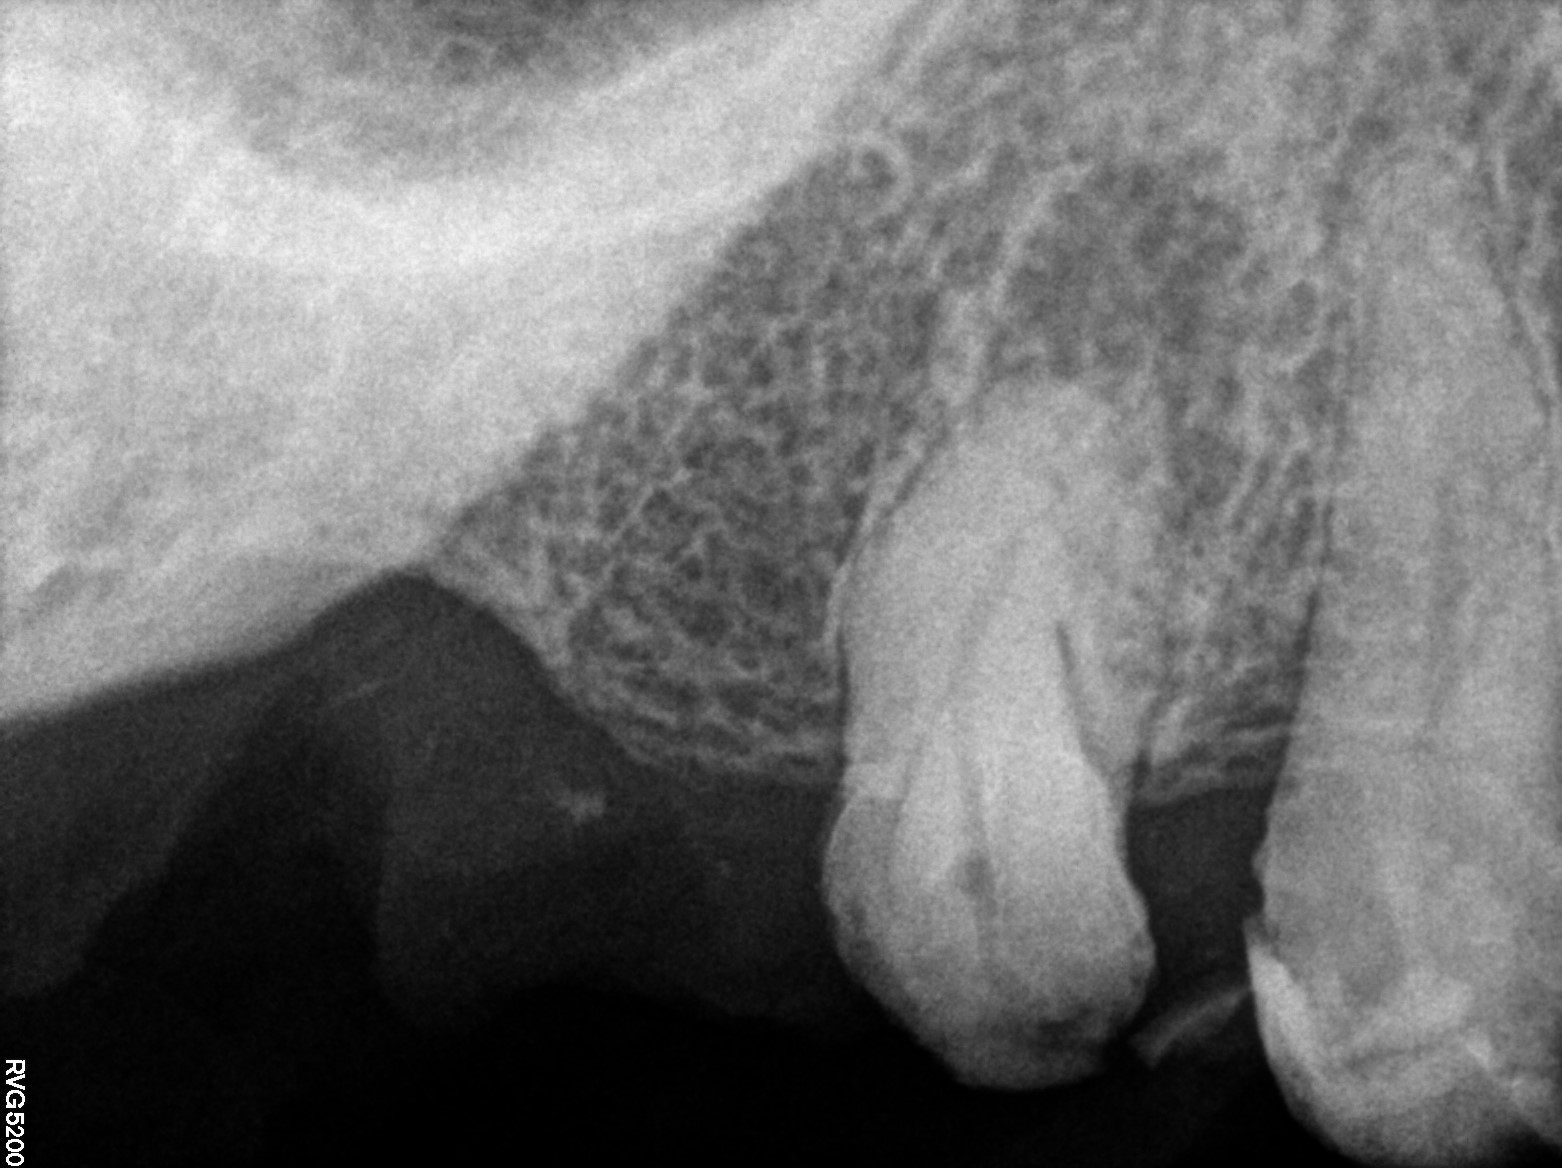

Dental Radiographs FHIR: DocumentReference · LOINC 24641-7

R61.jpg

24641-7

R65.jpg